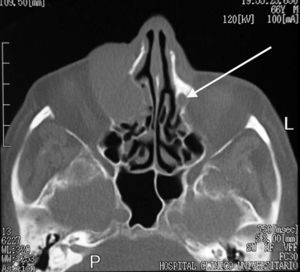

Fig. 4.--Resonancia magnética realizada tras la resección parcial del tumor. Corresponde a un plano coronal, potenciado en T2, en el que se pone de manifiesto la infiltración de la grasa orbitaria. Como hallazgo casual se observa una concha bullosa que se encuentra ocupada.

Se llevó a cabo una exéresis parcial de la lesión con fines diagnósticos y posteriormente se realizó una RM, que mostró (figs. 3 y 4) una mínima infiltración de la grasa orbitaria adyacente a la tumoración y descartó la afectación de la musculatura extrínseca ocular.